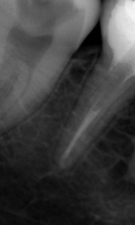

В стоматологической клинике "5 Принципов" в Симферополе мы гордимся тем, что каждый пациент получает индивидуальный подход и безупречный результат в области эндодонтического лечения под микроскопом. Наши специалисты применяют современные цифровые технологии, микропроцессорные и нейромодуляционные инструменты, что позволяет достичь максимальной точности и минимального дискомфорта. В портфолио клиники — широкий спектр кейсов: от первичной диагностики пульпита до сложной ретенированной резорбции и повторной эндодонтии. Мы беремся за зубы любых степеней сложности: от моляра до резцов, используя щадящие концевые инструменты и безболезненные методы постоянной анестезии. Все процедуры проходят под увеличением, что обеспечивает точное удаление инфицированной ткани и сохранение естественной анатомии зуба.Особое внимание мы уделяем постпроцедурному наблюдению: контроль за герметичностью заполнения корневых каналов, профилактические рекомендации и возможная корректировка плана лечения при необходимости. В "5 Принципах" мы разумно сочетаем комфорт, эстетическую привлекательность и долгосрочную функциональность. Результат — здоровые зубы, уверенная улыбка и спокойствие наших пациентов в Симферополе. Запишитесь на консультацию и убедитесь сами в нашем подходе к качественному эндодонтическому лечению.